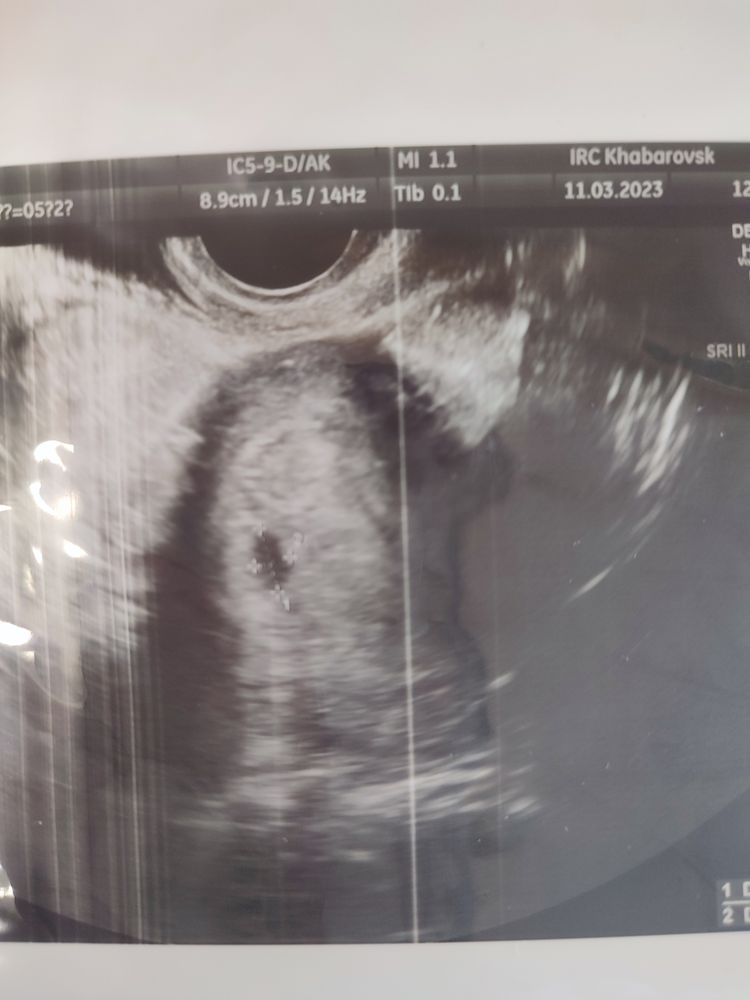

Нашли ПЯ, срок 5 недель и 2 дня акушерский

Изображение На память оставлю в дневнике)